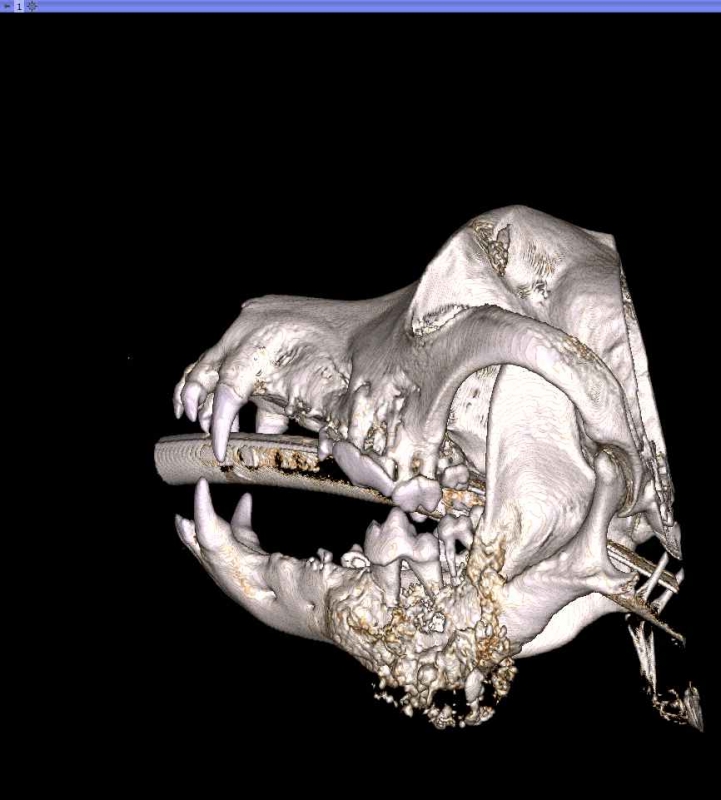

The Center now provides advanced imaging via cone beam CT. Cone beam CT is excellent for visualization of bony structures of the skull, nasal cavity, teeth, and ears. Cone beam CT is especially helpful for diagnosing dental disease and evaluation of jaw fractures. It can also be useful for evaluating the sinuses and tympanic bulla. Cone beam CT can be used in conjunction with nasal biopsy and culture to evaluate nasal discharge whether chronic or acute.

Repair of Maxillofacial Fracture

Pets can be involved in trauma that can cause fractures to their head, teeth, and jaw bones. Correctly repairing these fractures is extremely important for your pet to have normal function of their mouth. If a jaw fracture is allowed to heal in an abnormal position, your pet may have great difficulty chewing and can be in significant pain. Many fractures can be successfully treated with minimally invasive oral procedures, but more complicated cases may require bone plating techniques. The Center offers cone beam CT imaging which provides extremely detailed images of the bones of the head and skull. Advanced imaging with CBCT facilitates selection of the best surgical technique to get your pet back to eating and comfort as soon as possible.